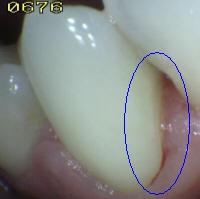

Con el fin de utilizar los criterios ICDAS en la práctica clínica las siguientes condiciones son esenciales para permitir a los examinadores evaluar cada uno de los códigos de caries con precisión:

• Remueva la placa dento-bacteriana de la superficies lisas y oclusales por medio de un cepillo dental y lave la zona con jeringa triple

• Remueva las manchas superficiales  y el cálculo dental de las superficies dentarias